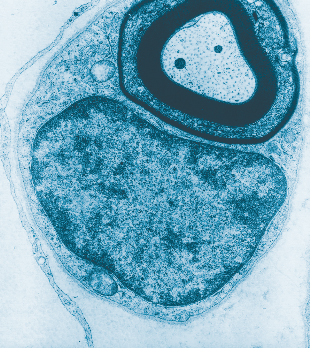

Ç÷°ü ³»ºÎ¸¦ ÀÌ·ç´Â ¡®³»ÇǼ¼Æ÷¡¯

Ç÷¾×ÀÇ È帧 µ½°í Ç÷°ü º®ÀÇ Ã»°á À¯Áö½ÃŰ´Â ¼¼Æ÷ <»çÁø¼³¸í = Ç÷°ü ´Ü¸éÀ» Àß¶ó º¸¸é ¾î´À °÷ÀÌµç ³»ÇǼ¼Æ÷(û»ö)°¡ °üÂûµÈ´Ù. ÀüÀÚÇö¹Ì°æ»çÁø 2000¹è È®´ë> .... ¤ÓÀ̹̳ª ±âÀÚ 2010-06-18